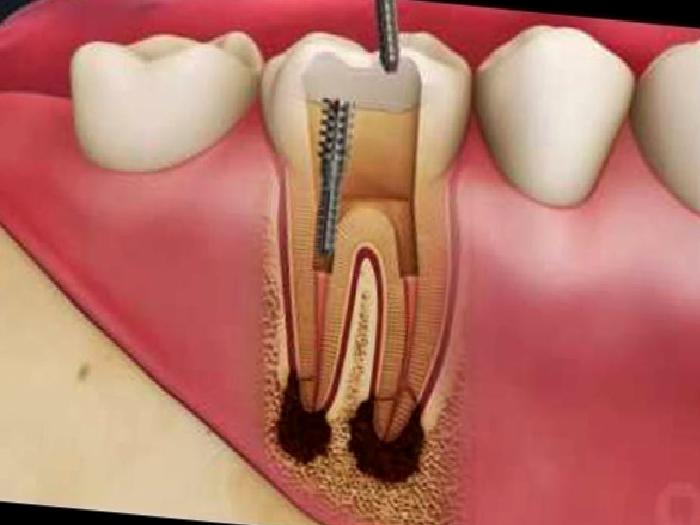

Hastalarımızdan alınan sözlü anamnez, ağız içi kontroller ve röntgen kontrolleri sonrası dişe kanal tedavisi işlemi gerekip gerekmeyeceğine karar verilir ve tedavi süreci başlar. İşleme başlamadan önce lokal anestezi uygulaması yapılmakta, hastanın ağrı hissetmesi önlenmektedir.Tedavi sırasında dişin varsa çürükten etkilenmiş kısmı uzaklaştırılır, pulpa odası açılır ve diş kökleri içindeki ağrı hissedilmesini sağlayan sinirler uzaklaştırıldıktan sonra kök kanallarının gereken şekillendirilmesi yapılır. Kanalların içindeki bakteri ve artıkların dezenfeksiyonunu sağlamak için bazı solüsyonlar ile kanal içi yıkanır, kurutulur. Kök kanalları çeşitli kanal dolgu malzemeleri ile kök ucuna kadar doldurulur ve dişin ağız içinde görünen kron kısmının restorasyonu yapılmaktadır.

Kanal tedavisi işlemi, dişteki enfeksiyonun durumuna göre 30- 60 dakikalık tek seansla yapılabileceği gibi enfeksiyon kemik dokuda fazla yayılım göstermişse birden fazla seans da gerekebilmektedir. Birden fazla seans gereken durumlarda seanslar arasında kök kanallarının içine iyileşmeye yardımcı bir malzeme yerleştirilip ağız içi ile bağlantısını kesmek için diş içine de geçici bir dolgu materyali uygulanmaktadır.